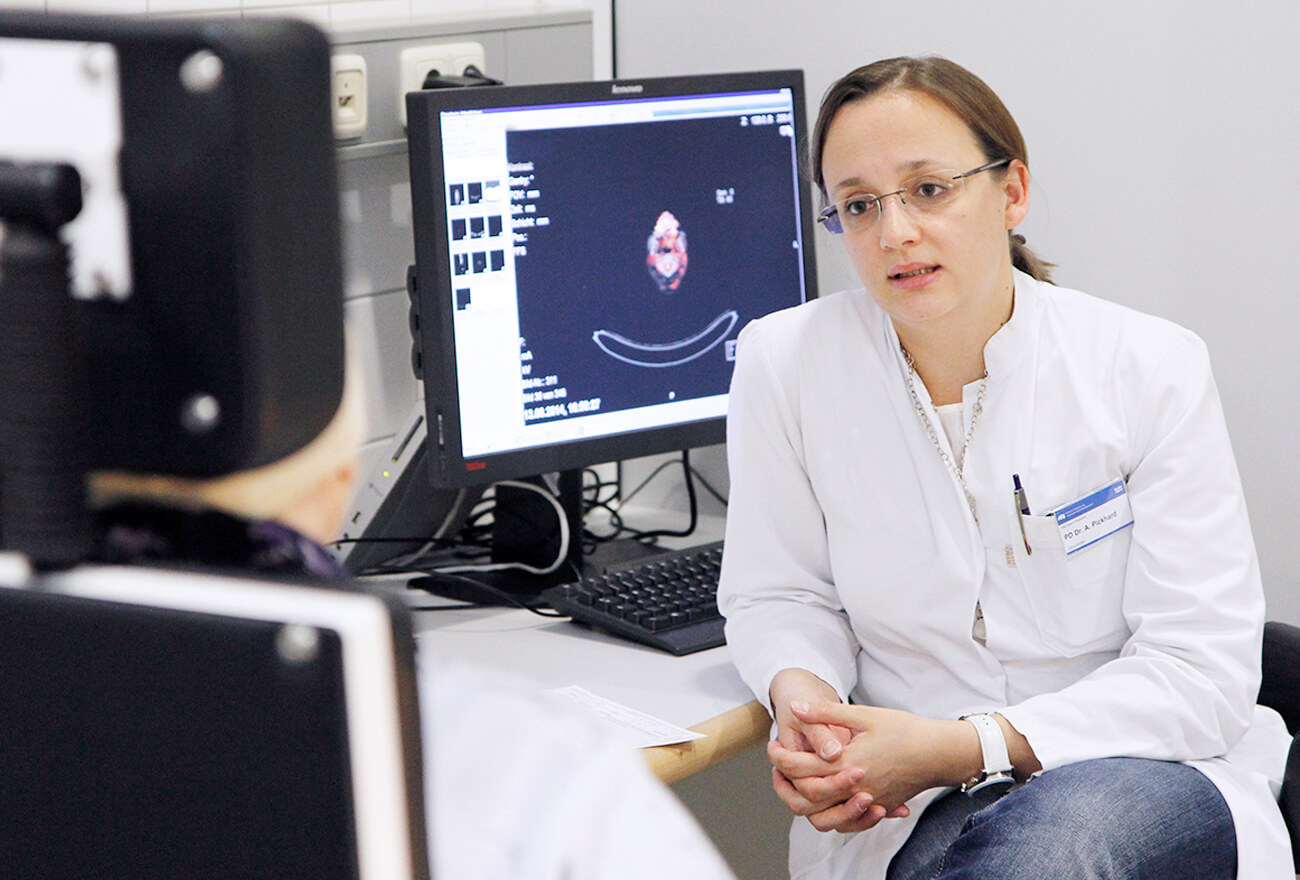

Therapie von Schilddrüsenerkrankungen Ist es wirklich sinnvoll, was

Diagnostik und Untersuchungstechniken

SchilddrüsenDiagnostik DIE RADIOLOGIE München

Schilddrüsenszintigraphie bei der Radiologie München